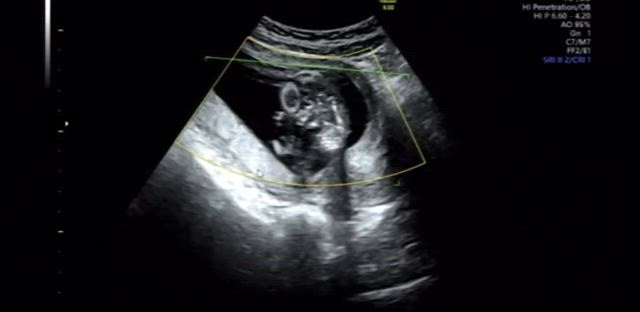

16w6d 妊婦検診♥性別分かりました